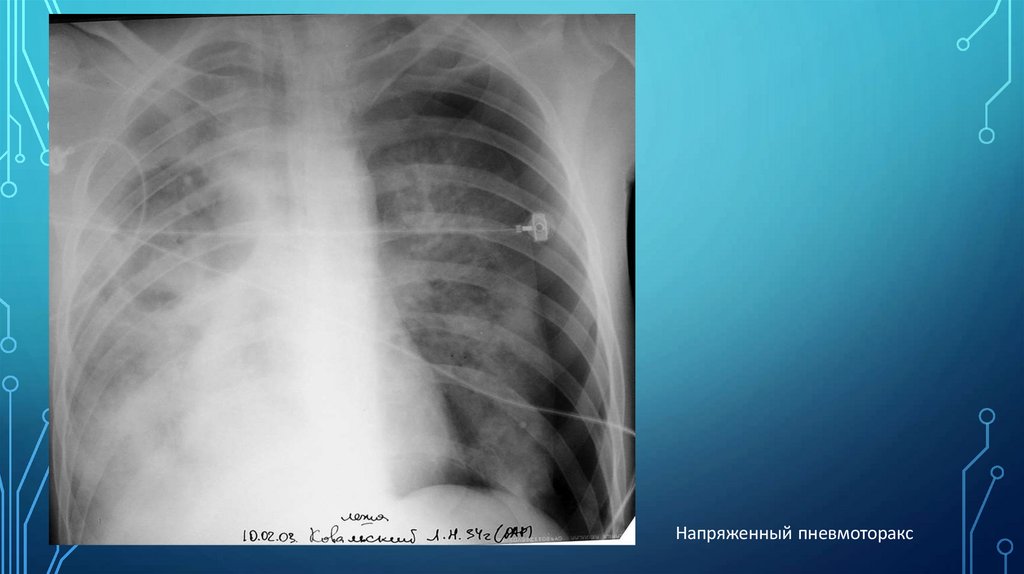

Напряженный пневмоторакс

Внелегочный патологический процесс–

тотальный пневмоторакс, который

характеризуется:

Значительным

просветлением

периферической

части гемиторакса

Полным отсутствием в этой зоне легочного рисунка

Пневматизация спавшегося легкого уменьшена

Легкое уменьшено и смещено к корню, благодаря

чему хорошо виден его латеральный контур

(Картина более наглядна в фазе выдоха)

При

напряженном

пневмотораксе

средостение

смещается в противоположную сторону, а диафрагма

вниз